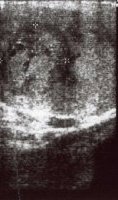

Die Hodenfreilegung und Probeentnahme zur Schnellschnittuntersuchung bestätigte den Hodentumorverdacht. Intraoperativ zeigte sich bei Eröffnung der Tunica albuginia über dem tumorverdächtigen Areal ein umschriebener Tumorknoten von inhomogener Schnittfläche mit zum Teil zystischen, schleimbildenden, gefäßreichem Gewebe (Abbildung 13).

Die histologische Untersuchung ergab embryonales Karzinom, Teile von Dottersacktumor und herdförmige Strukturen eines reifen und unreifen Teratoms (MTI). Postoperativ fielen die Tumormarker ab (Abbildung 12). Eine Lymphadenektomie ergab keinen Tumornachweis. Anschließend erhielt der Patient 3 Zyklen BEP.